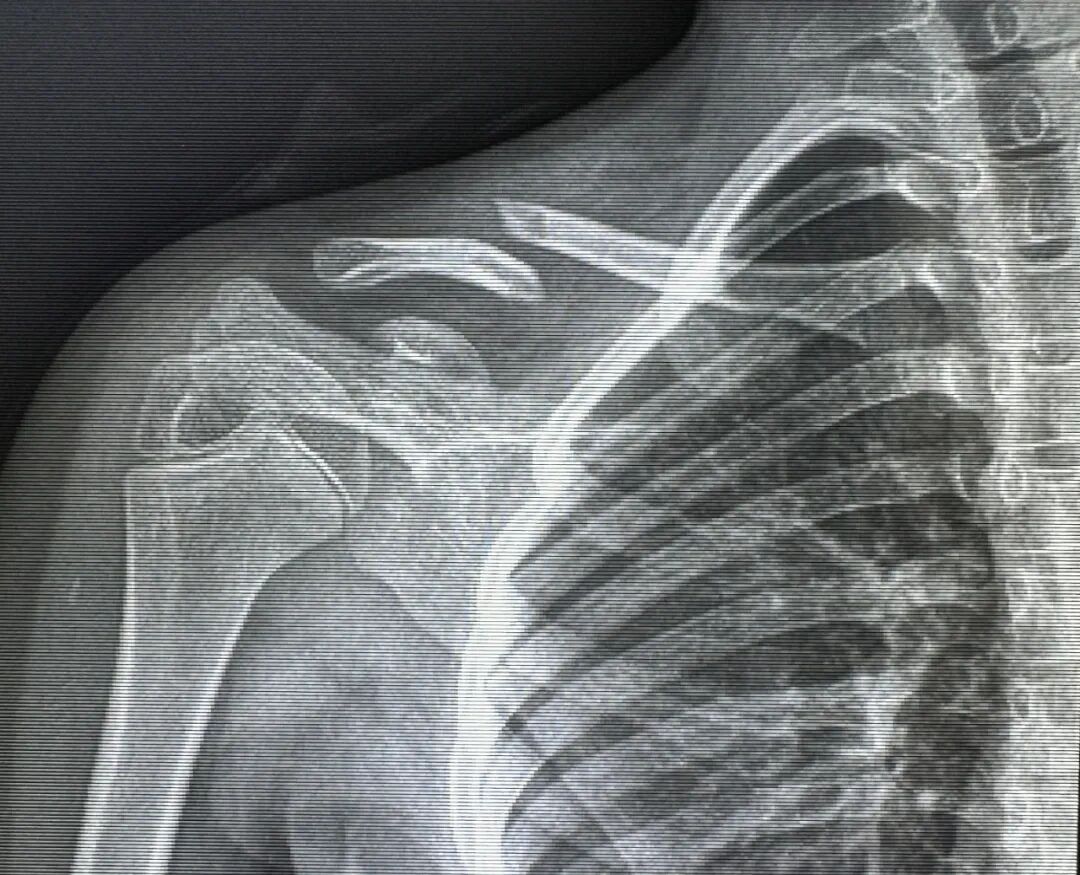

• 【卓越医疗】微创技术治疗青少年锁骨骨折——不开刀,“针”不错!

【卓越医疗】微创技术治疗青少年锁骨骨折——不开刀,“针”不错!

图文 发布时间:2024-11-20 09:16:08